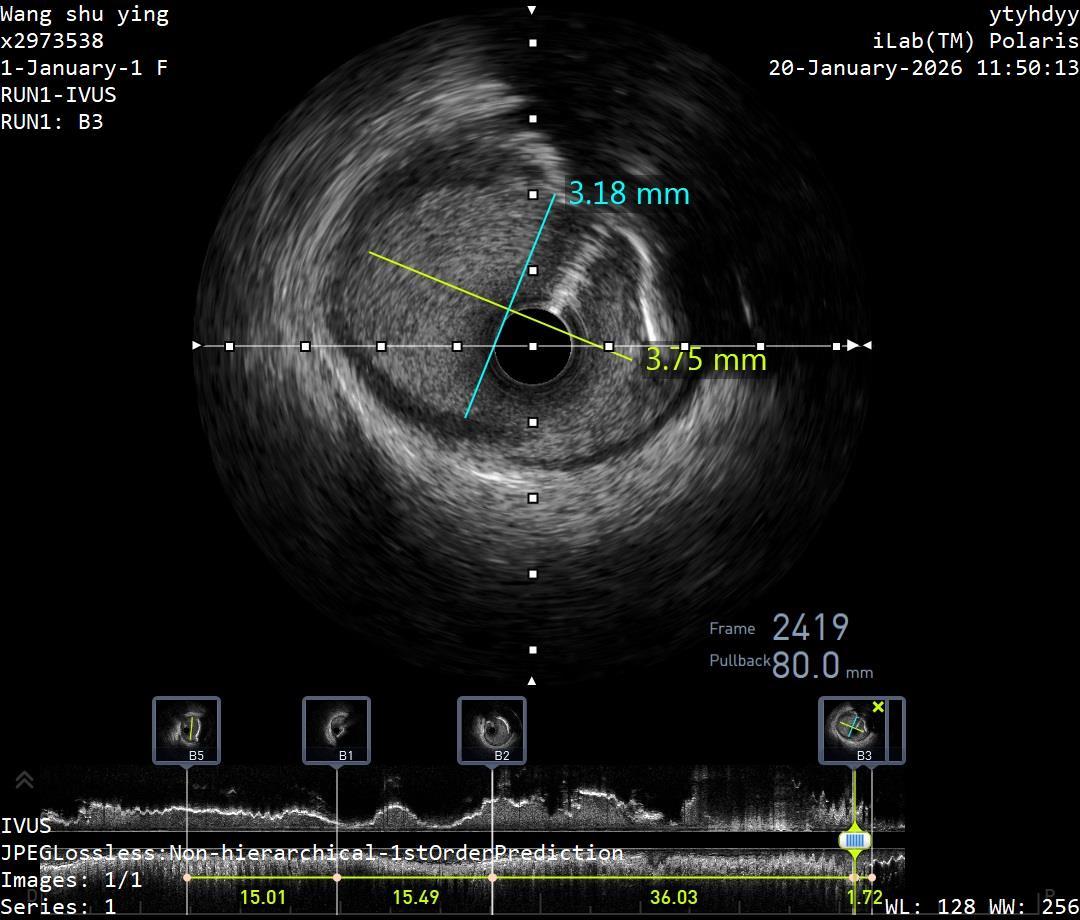

IVL术后腔内影像

患者为70岁男性,急性冠脉综合征入院,伴2型糖尿病、高血压病3级(极高危)等。造影见左前降支近段约90%狭窄,第一对角支近段约50%狭窄;IVUS下可见360°环形钙化。宋年朋、潘洋手术团队评估后选择了冲击波球囊技术,冲击波球囊技术在环形钙化的预处理上有不可取代的优势,且安全性高,手术风险相对较低。团队在IVUS引导下,冲击波球囊精准定位后,进行了7个周期(每周期10次)治疗,冲击波球囊治疗后IVUS下可见钙化环断裂。随后植入药物洗脱支架,远端TIMI血流3级,手术顺利结束。